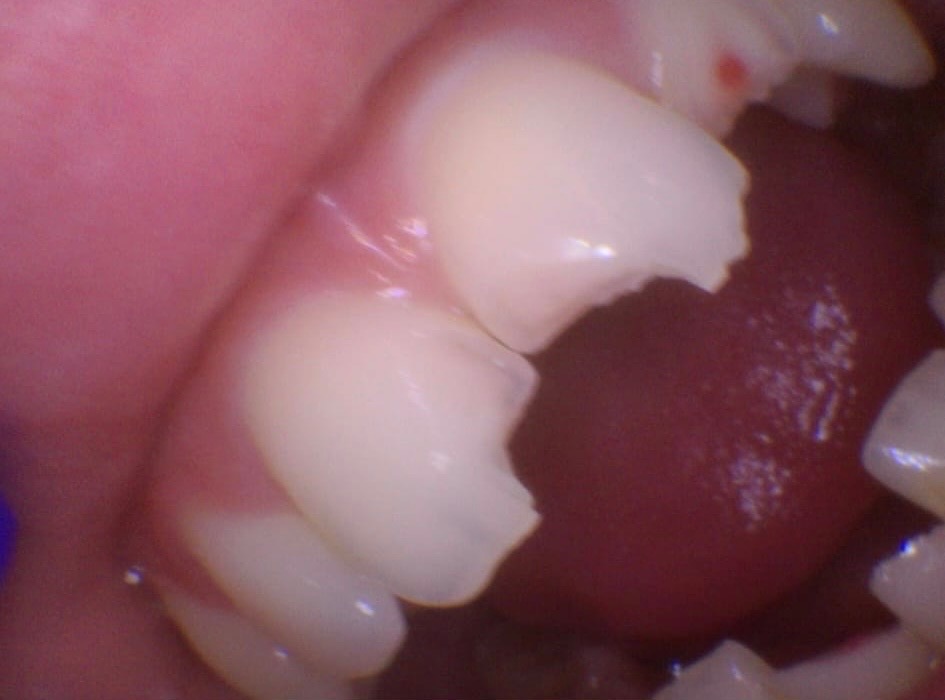

Kaiden suffered a bruised cheekbone, a black eye, concussion and extensive trauma to his teeth.

Altogether, he has six broken teeth.

Kaiden needs:

5 root canals

5 dental caps

1 tooth implant

Specialist surgery, as one tooth has shattered in several places inside the jaw and cannot be removed without a surgical procedure

The implant alone costs £3,000 and will not be funded by the NHS, this amount doesn’t include the significant work needed on the other five teeth.